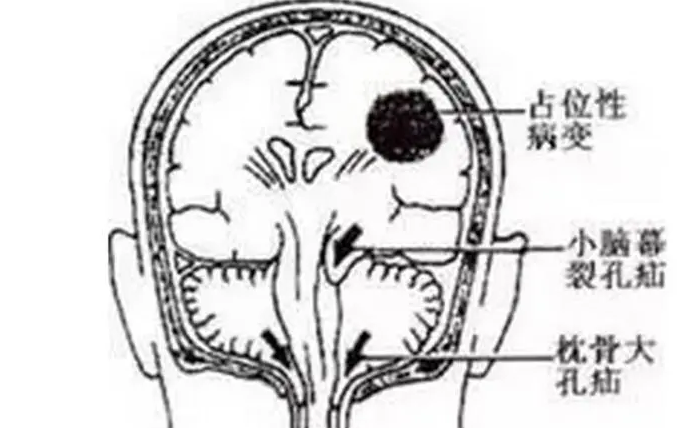

所谓“占位性病变”实际上它是医学诊断学当中的一个专用名词。通常是出现在X线、B超、CT等等检查报告当中,是指被检查的部位里面有多出来的东西,这个多出来的东西呢,可使周围组织可能受压、移位。那么什么是占位性病变呢,通常呢,在我们这里可能是泛指肿瘤,当然这里有良性的,也有恶性的,还有一些寄生虫等等不涉及疾病的病因,所以占位性病变并不等于癌症。